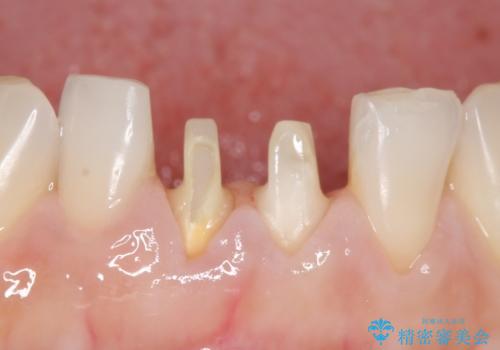

- 下顎前歯の見た目が気になるといらっしゃった方の症例です。

右下1の再根管治療終了後、オールセラミッククラウン(スペシャル)による補綴を行いました。